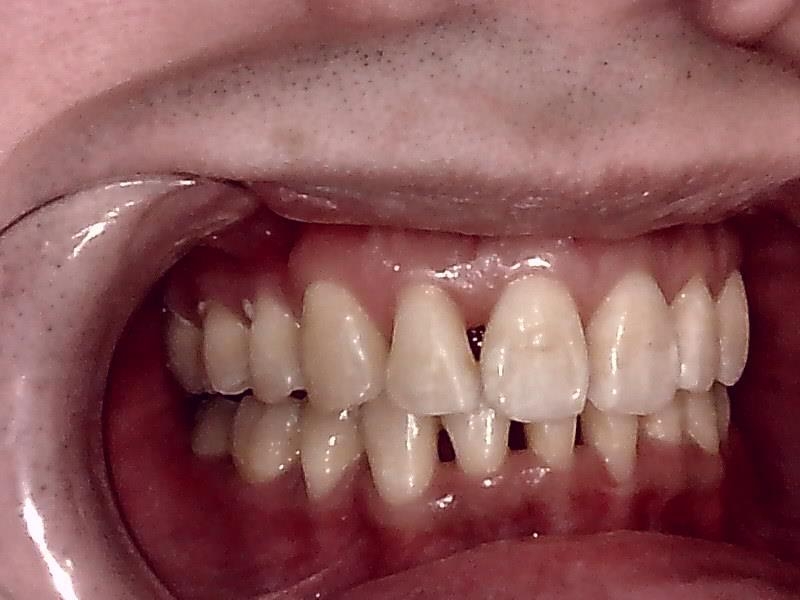

左側

右側

右側 術前の写真